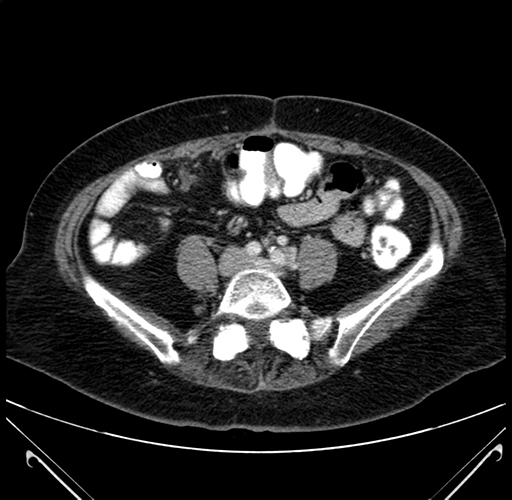

Pre-Chemo: Axial Venous

Axial Venous